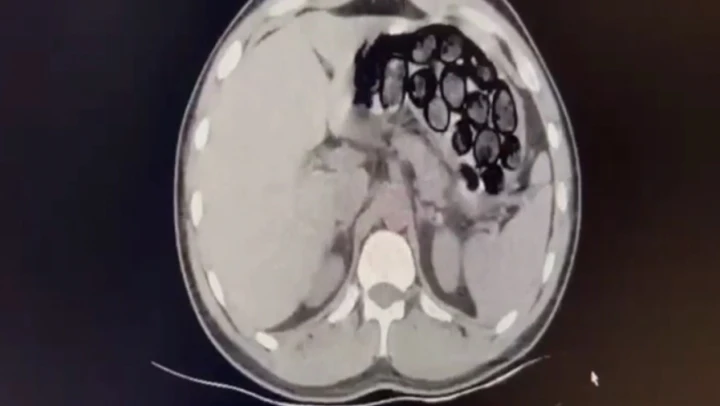

Jandarma ekiplerince takibe alınan İranlı şahıs ve beraberindeki 2 kişi, Kars'ın Selim ilçesi girişinde ticari takside yakalandı. Yapılan üst aramasında bir şey bulunamayan Omid Baghernezad, Kars Harakani Devlet Hastanesi'ne götürüldü. Burada çekilen röntgende Omid Baghernezad'ın mide ve bağırsağında kapsüller halinde 65 parça halinde 412 gram sentetik uyuşturucu olduğu belirlendi.